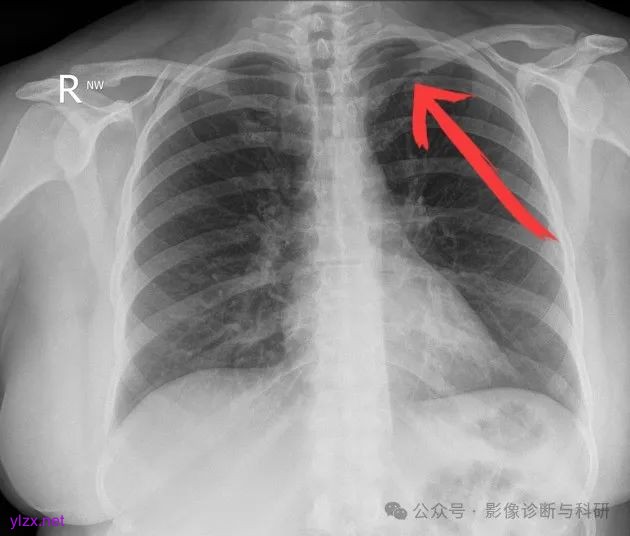

左侧锁骨菱形窝凹陷